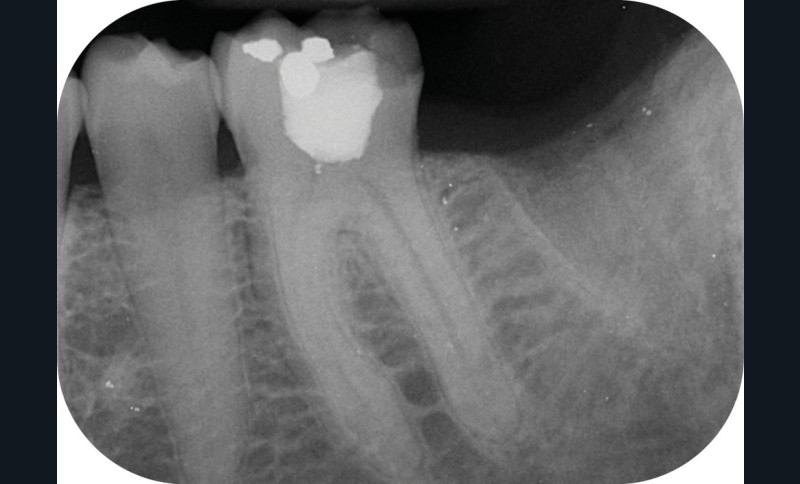

- la nature des alliages. Au début dans leur composition, et plus tard avec des traitements thermiques qui ont permis d’améliorer encore la souplesse lorsque l’évolution des « design » n’était plus possible (fig. 1).

Au moment de la rédaction de ce document, dix-huit systèmes de mise en forme canalaire sont commercialisés sur le marché français. Toutes les publicités promeuvent des améliorations de l’efficacité, de la souplesse et surtout de la résistance à la fracture (fig. 2). Il faut reconnaître que même si ces systèmes sont très différents, les résultats obtenus sont finalement assez constants, et il faudrait des études très poussées pour démontrer la supériorité de l’un par rapport à l’autre (si tant est qu’il y en ait une !).